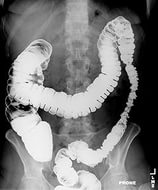

Часто застосовується також рентгенографічний метод. Пацієнту дають випити речовину, непроникну для рентгенівських променів. Потім при просвічуванні на рентген-апараті визначають контури різних відділів травного тракту.